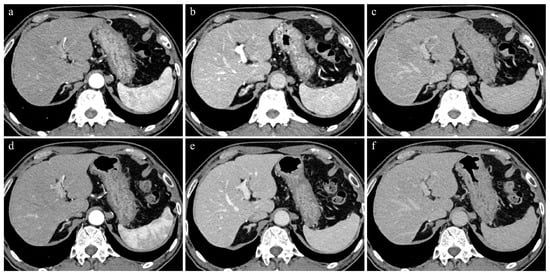

Figure 1. A 74-year-old man with 62.3kg body weight. (ac) Initial CT images obtained with 70 kVp protocol during AP (a), PVP (b), and EP (c). (df) Follow-up CT images (9 months later) obtained with blended DE protocol during AP (d), PVP (e), and EP (f). All CT images were reconstructed by IR methods. Contrast enhancement of the hepatic parenchyma, portal vein, and hepatic vein in PVP and EP were better in 70 kVp than in blended DE protocol.

Table 1 shows the results of the comparison of quantitative image assessments between the two protocols. The median CT values (HU) of the hepatic parenchyma in the 70 kVp protocol were significantly higher than those in the blended DE protocol in all three phases (AP: 86.0 HU vs. 77.1 HU, p < 0.001; PVP: 119.8 HU vs. 108.0 HU, p < 0.001; EP: 101.9 HU vs. 91.4 HU, p < 0.001, respectively) (Figure 1). Conversely, median image noises (background SD) were significantly lower in the blended DE than in the 70 kVp protocol in the PVP (7.33 vs. 7.75, p = 0.002), while their differences were not statistically significant between the blended DE and 70 kVp protocols in the AP and EP (AP: 7.07 vs. 7.70, p = 0.118; EP: 7.19 vs. 7.33, p = 0.10, respectively). Regarding the CNR and the SNR, there were no significant differences between the 70 kVp and blended DE protocols in the CNR (AP: 3.5 vs. 2.8, p = 0.93; PVP: 7.3 vs. 6.4, p = 0.88; EP: 4.8 vs. 4.7, p = 0.65, respectively) or SNR (AP: 11.5 vs. 11.1, p = 0.44; PVP: 14.9 vs. 15.4, p = 0.39; EP: 13.7 vs. 13.3, p = 0.36, respectively) of the liver parenchyma in all three phases.

Regarding the overall image quality, it was significantly better in the 70 kVp than in the blended DE protocol in the AP (4.0 vs. 4.0, p = 0.035) and EP (3.0 vs. 3.0, p = 0.016) (Figure 1). Conversely, the median image noise scores were significantly better in the blended DE than in the 70 kVp protocol in all phases (AP: 4.0 vs. 3.5, p < 0.001, PVP: 4.0 vs. 4.0, p = 0.046, EP: 4.0 vs. 3.0, p = 0.004, respectively).

In the comparison in clarity of contrast between the hepatic parenchyma and portal vein in the PVP and between the hepatic parenchyma and hepatic vein in the EP, the median scores in the 70 kVp protocol were significantly higher than those in the blended DE protocol (5.0 vs. 4.0, p < 0.001; 3.0 vs. 2.0, p < 0.001, respectively) (Figure 1).